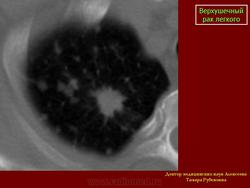

Верхушечный рак легкого

Рентгенологическую симптоматику опухолевого поражения верхушечного сегмента легкого в виде “апикального колпака” с развитием клинического синдрома, обусловленного сдавлением или прорастанием плечевого сплетения, сопровождающегося интенсивными, постоянными болями в верхней конечности и лопатке, впервые описал Pancoast H. (1924г., 1932г.).

Клиническая картина и стадийность процесса при верхушечном раке легкого зависит от преимущественного направления роста опухоли, поэтому принято выделять синдром Панкоста полный (с характерным клинико-неврологическим синдромом) и неполный.

Различают 4 типа вовлечения нервной системы в опухолевый процесс, в зависимости от прорастания тканей надплечья и грудной стенки: 1тип - поражение нижнего шейного симпатического ганглия, что приводит к триаде Горнера, нарушению потоотделения в верхней конечности, болям каузалгического характера. II тип - поражение нижнего ствола плечевого сплетения и I-II грудного нерва, обуславливает боли в плечевом поясе с иррадиацией в руку, слабость мышц, расстройство чувствительности и нарушение рефлексов в верхней конечности пораженной стороны. III тип - вовлечение в процесс возвратного нерва, что приводит к осиплости голоса. IV тип - поражение спинного мозга, возникает при прорастании опухоли в позвоночный канал. Возможно вовлечение в процесс диафрагмального нерва, при котором наступает паралич соответствующего купола диафрагмы.

При верхушечном раке на первых этапах развития заболевание может протекать бессимптомно и опухоль обнаруживается при профилактической флюорографии. Иногда больные отмечают острое начало болезни, которое сопровождается гектическим подъемом температуры тела и даже кровохарканьем. При постепенном развитии болезни ведущим клиническим симптомом является боли в груди, сроки от момента появления первых симптомов заболевания до установления диагноза колеблются от 1 до 4х месяцев, иногда могут затягиваться до 6 месяцев. Больным без проведения рентгенологического исследования органов грудной клетки, назначается физиотерапевтическое лечение по поводу предполагаемого остеохондроза грудного отдела позвоночника.

Рентгенологические проявления верхушечного рака легкого обусловлены стадийностью его роста, при которой можно выделить 2 группы.

Первая группа: верхушечный рак без синдрома Панкоста - опухоль не выходит за пределы легочной ткани. Опухолевые узлы округлой или неправильной формы, различных размеров, однородной структуры с бугристой поверхностью и нечеткими контурами, которые в виде тяжей распространяются в прилежащие отделы легочной ткани.Может выявляться неоднородная дорожка к корню легкого в результате перибронхиального роста опухоли в сторону корня, при этом отмечается неравномерное сужение просвета сегментарного бронха.

Следует отметить, что при железистых раках (АДКЛ) опухоль длительное время не выходит за пределы легочной ткани и не вызывает клинико-неврологических синдромов, однако, выявляются регионарные и отдаленные метастазы. Метастатическое поражение может проявляться увеличением ипсилатеральных лимфатических узлов корня легкого и средостения, над - и подключичных областей, иногда диссеминированным поражением легочной ткани.

Вторая группа: верхушечный рак с синдромом Панкоста. Клиническая картина характеризуется присоединением неврологической симптоматики различной степени выраженности. При рентгенологическом исследовании выявляется распространение опухолевого процесса за пределы легочной ткани, с вовлечением прилежащих структур средостения, мягких тканей грудной стенки, ребер и позвонков. Размеры опухолевых узлов от 3,0 см и более, имеющих округлую, овальную или неправильную форму, структура их однородная или неоднородная. Наружные контуры нечеткие, за счет распространения опухолевой инфильтрации на прилежащие органы и ткани: плевру, мягкие ткани грудной стенки, ребра, средостение, позвонки. Внутренняя поверхность опухоли может быть крупнобугристая с четкими, неровными или нечеткими контурами.

Неоднородность структуры опухоли обусловлена обычно неравномерной плотностью узла, иногда деструкцией опухолевой ткани с формированием полости распада.

Истинная степень распространенности опухолевого процесса на прилежащие ткани средостения, ребра и позвонки устанавливается при проведении МРТ исследования.

Следует отметить, что имеются различия в клинико-рентгенологических проявлениях верхушечного рака в зависимости от гистологического строения опухоли.Так при ПКРЛ преобладает местное распространение опухолевого процесса, а при АДКЛ выявляются отдаленные метастазы, появление которых не зависит от размеров первичной опухоли.

Ошибки диагностики верхушечного рака легкого на поликлиническом этапе в 20% обусловлены неполноценным обследованием больных и в 30% неправильной оценкой рентгенологической картины. Снижение уровня диагностических ошибок может быть достигнуто благодаря проведению рентгенологического исследования органов грудной клетки при первичном обращении больного за медицинской помощью.

Таким образом, в установлении диагноза верхушечного рака легкого основная роль принадлежит лучевым методам исследования. Учёт особенностей клинических проявлений заболевания и рентгенологической картиной должны улучшить диагностику этой периферической опухоли легкого.